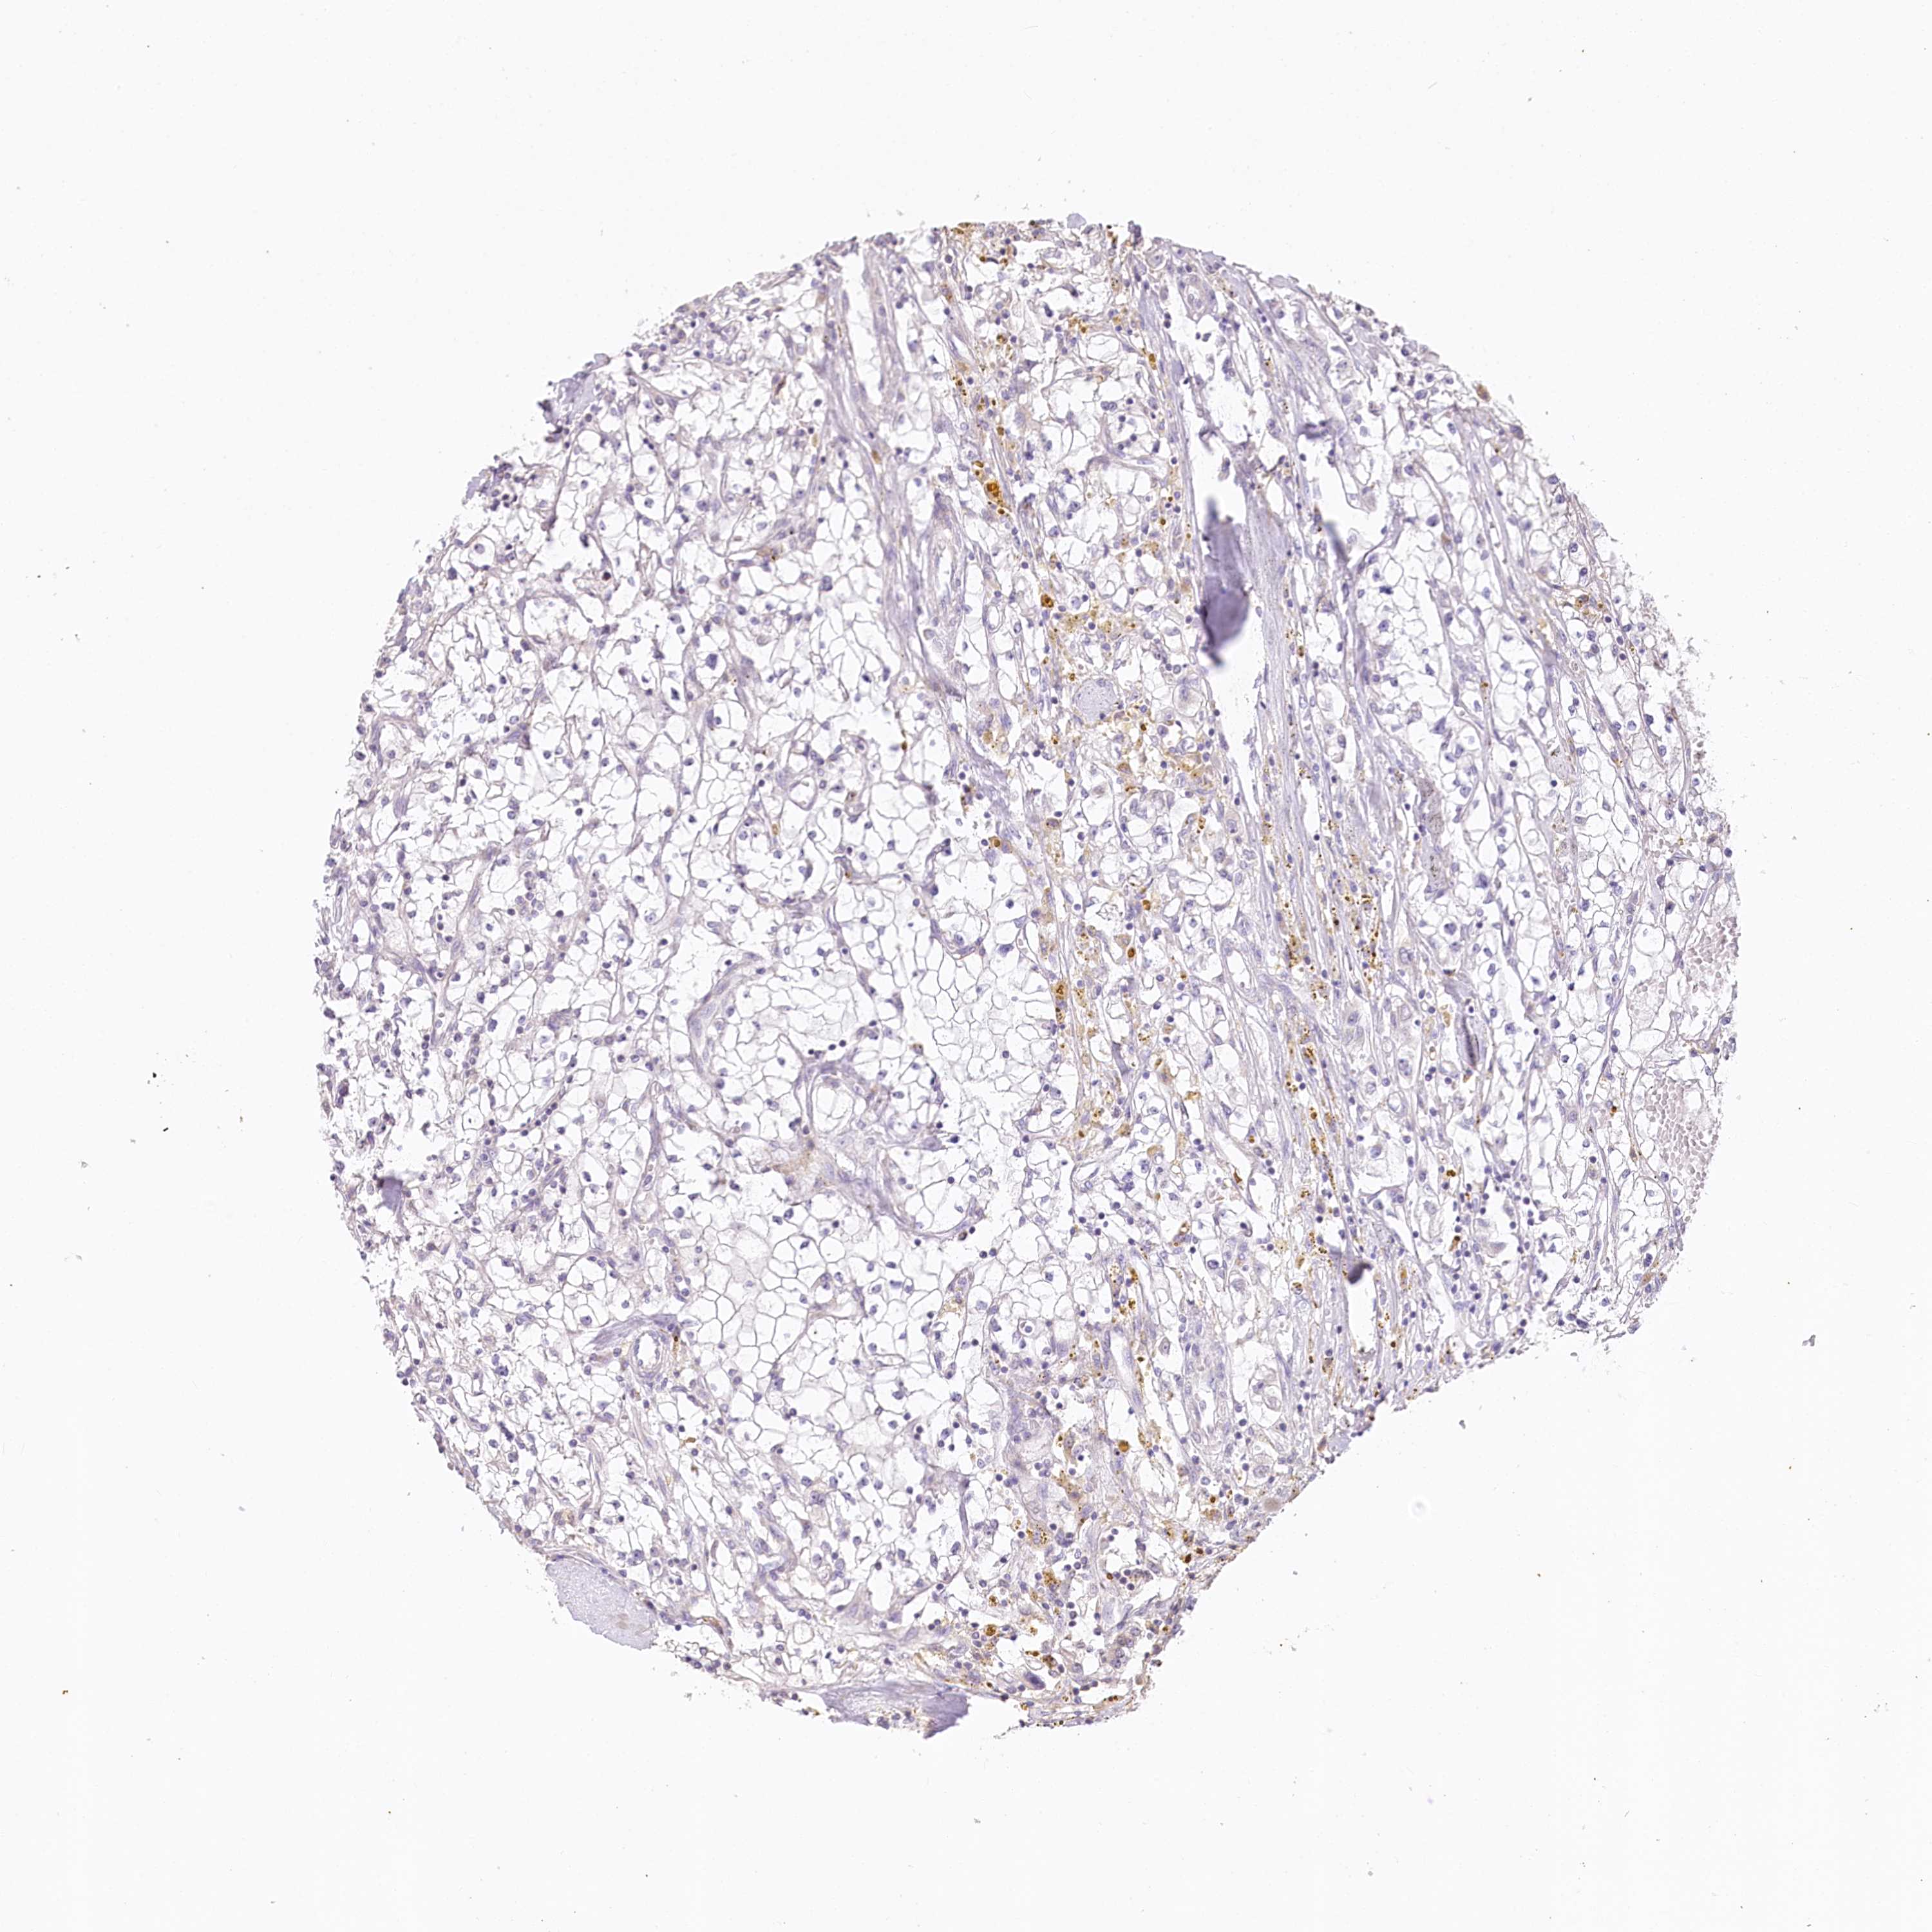

KIDNEY RENAL CLEAR CELL CARCINOMA (VALIDATION) - Interactive survival scatter ploti

The Survival Scatter plot shows the clinical status (i.e. dead or alive) for all individuals in the patient cohort, based on the same data that underlies the corresponding Kaplan-Meier plots. Patients that are alive at last time for follow-up are shown in blue and patients who have died during the study are shown in red.

The x-axis shows the expression levels (FPKM) of the investigated gene in the tumor tissue at the time of diagnosis. The y-axis shows the follow-up time after diagnosis (years). Both axes are complimented with kernel density curves demonstrating the data density over the axes. The top density plot shows the expression levels (FPKM) distribution among dead (red) and alive patients (blue). The right density plot shows the data density of the survived years of dead patients with high and low expression levels respectively, stratified using the cutoff indicated by the vertical dashed line through the Survival Scatter plot. This cutoff is automatically defined based on the FPKM cutoff that minimizes the p-score. The cutoff can be changed by dragging the vertical line or by entering a cutoff value in the square labeled "Current cut-off".

Under the Survival Scatter plot the p-score landscape (black curve; left axis) is shown together with dead median separation (red curve; right axis). Dead median separation is the difference in median mRNA expression between patients who have died with high and low expression, respectively. It is calculated as follows: median FPKM expression of dead patients with high expression - median FPKM expression of dead patients with low expression. This is intended to aid the user in visually exploring custom cutoffs and the associated p-scores and dead median separation.

Individual patient data is displayed and can be filtered by clicking on one or more of the category buttons on the top of the page. Categories describing expression level and patient information include: high, low, alive, dead, female, male and tumor stages. The scale of the x-axis can be toggled between linear and log-scale by clicking on the "x log" button. Mouse-over function shows TCGA ID, patient information and mRNA expression (FPKM) for each patient.

& Survival analysisi

Kaplan-Meier plots summarize results from analysis of correlation between mRNA expression level and patient survival. Patients were divided based on level of expression into one of the two groups "low" (under cut off) or "high" (over cut off). X-axis shows time for survival (years) and y-axis shows the probability of survival, where 1.0 corresponds to 100 percent.

ZNF226 is not prognostic in Kidney Renal Clear Cell Carcinoma (validation)